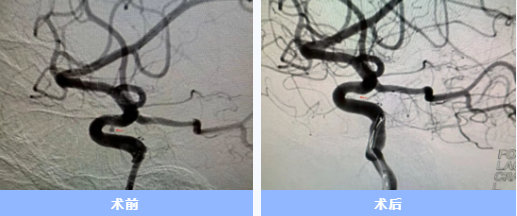

人的大腦里,有時(shí)候血管會悄悄鼓起一個(gè)“小泡”,它就像一顆“不定時(shí)炸彈”,一旦破裂就會危及生命。近日,隨州市中心醫(yī)院神經(jīng)內(nèi)科團(tuán)隊(duì)成功通過手腕橈動脈穿刺入路,為6位顱內(nèi)動脈瘤患者完成介入栓塞手術(shù)。6位患者均已轉(zhuǎn)危為安,其中3人康復(fù)出院,3人在院恢復(fù)中。

入院后急診完成了頭頸部血管檢查,卻未發(fā)現(xiàn)動脈瘤。神經(jīng)內(nèi)科一病區(qū)負(fù)責(zé)人胡蘇華當(dāng)晚緊急為患者做了更精確的腦血管造影,終于發(fā)現(xiàn)右側(cè)頸內(nèi)動脈上藏著一個(gè)極其微小的動脈瘤——直徑僅約1毫米左右,堪稱從醫(yī)二十多年來遇見的最難發(fā)現(xiàn)的"炸彈"。

手術(shù)當(dāng)天,胡蘇華與主治醫(yī)師陳浩協(xié)作,首先經(jīng)患者右手橈動脈成功建立治療通道,隨后才實(shí)施全身麻醉,以最大限度縮短麻醉時(shí)間。憑借精湛技藝,團(tuán)隊(duì)迅速而完整地栓塞了動脈瘤。術(shù)后患者很快在ICU蘇醒,四肢活動良好,第二天即返回普通病房。

顱內(nèi)動脈瘤就像是埋在顱內(nèi)的"不定時(shí)炸彈",傳統(tǒng)手術(shù)需從大腿股動脈穿刺,術(shù)后患者需平臥制動6-24小時(shí)。而經(jīng)手腕穿刺的介入治療,則大幅提升了患者舒適度——術(shù)后不需長時(shí)間臥床,可早期下地活動,恢復(fù)體驗(yàn)明顯改善。

隨州市中心醫(yī)院神經(jīng)內(nèi)科自2016年起獨(dú)立開展顱內(nèi)動脈瘤介入手術(shù),至今已有近十年經(jīng)驗(yàn),每年完成動脈瘤介入手術(shù)一百余例。此次在前期開展經(jīng)橈腦動脈造影及缺血性腦血管病治療的基礎(chǔ)上,常規(guī)開展經(jīng)橈治療顱內(nèi)動脈瘤,標(biāo)志著該院神經(jīng)介入真正實(shí)現(xiàn)"不僅微創(chuàng),更加舒適"。 (供稿通訊員:陳浩)